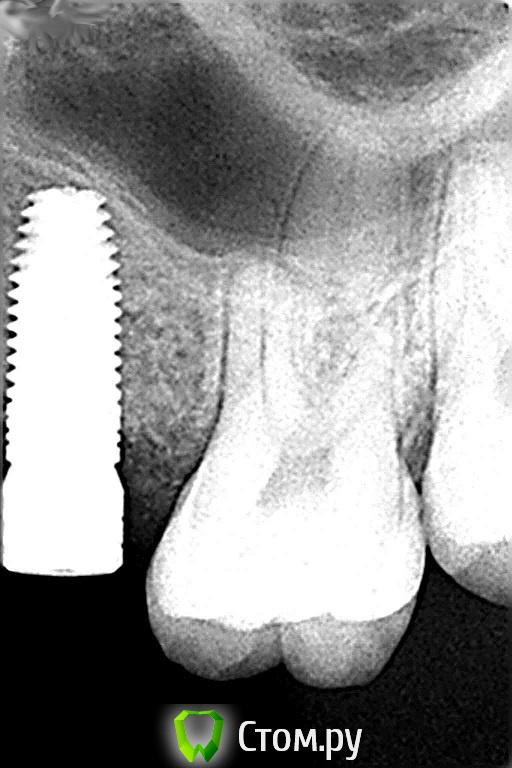

Михаил Демурчян Опубликовано 29 октября, 2014 Поделиться Опубликовано 29 октября, 2014 (изменено) Комментарии к фотографиям: 1. В тех случаях, когда нужно поднять пазуху всего на 2-3 мм, можно обойтись совершенно без остеопластического материала. Рентгенограмма до операции. 2. Рентгенограмма сразу после операции. Над установленным имплантатом виден фрагмент кости вследствие проведенной остеотомии. Тень полусферы обозначает границы кровяного сгустка под слизистой оболочкой пазухи. 3. Контрольный снимок спустя год после операции. Видна новая граница пазухи над имплантатом. Изменено 29 октября, 2014 пользователем Михаил Демурчян 4 Ссылка на комментарий